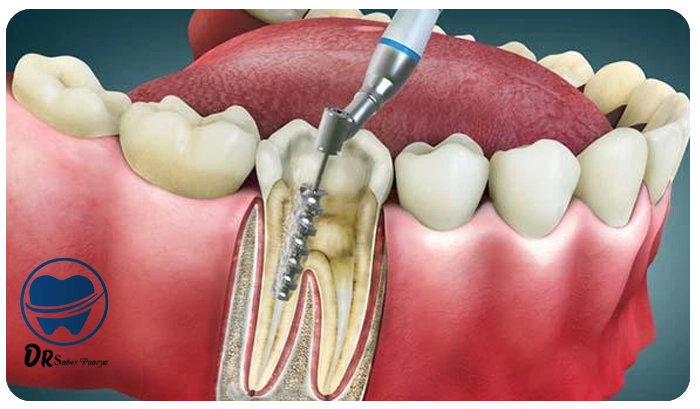

مراحل درمان ریشه (عصبکشی) معمولاً در چند گام دقیق و برنامهریزیشده انجام میگیرد.

هدف این فرآیند، حذف عفونت از داخل دندان و حفظ آن برای ادامه عملکرد طبیعی در دهان است.

بررسی اولیه و تصویربرداری دندان

برای شروع، دندانپزشک با استفاده از رادیوگرافی (عکسبرداری) دقیق، میزان آسیب و محل دقیق عفونت را بررسی میکند.

این مرحله کمک میکند تا مسیر درمان مشخص شود.

بیحسی و دسترسی به پالپ دندان

پس از معاینه، بیحسی موضعی برای ناحیه مربوطه تزریق میشود تا بیمار هیچگونه دردی احساس نکند.

سپس دندانپزشک با ایجاد حفرهای کوچک در تاج دندان، به ناحیه داخلی (پالپ) دسترسی پیدا میکند و قسمتهای پوسیده را حذف مینماید.

خارج کردن بافت عفونی

در این مرحله، بافت آسیبدیده و عفونی درون کانالهای ریشه بهطور کامل تخلیه میشود.

هدف، حذف کامل اعصاب و عروق داخل دندان است تا از بروز درد یا عفونت مجدد جلوگیری شود.

شستشو و پاکسازی کانالها

کانالهای دندان پس از تخلیه، باید با دقت ضدعفونی و پاکسازی شوند. برای این کار، محلولهای مخصوصی استفاده میشود

که هم باقیماندههای عفونی را از بین میبرند و هم به از بین رفتن باکتریها کمک میکنند.

پر کردن کانالها

بعد از پاکسازی کامل، دندانپزشک از مادهای خاص بهنام گوتاپرکا برای پر کردن کانالهای ریشه استفاده میکند.

سپس برای محافظت موقت از دندان، پانسمان موقتی روی آن قرار داده میشود.